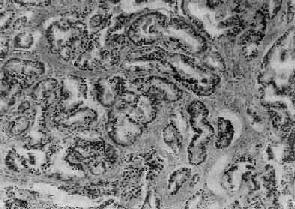

镜下,97%的前列腺均为腺,少数为移行细胞和鳞状细胞。依其分化程度可分为高分化、中分化和低分化3型。高分化前列腺最多见,细胞排列成大小不等的腺样结构,颇似前列腺增生腺体,但细胞体积较小,核较深染,上皮细胞往往呈多层排列并较不规则(图14-4),有时可呈乳头状腺或腺泡腺结构,并常可见组织向间质浸润生长;中分化腺全部或部分呈腺样结构,但腺体排列较紊乱,核异型性较明显,且有时形成筛状结构;低分化腺细胞一般较小,排列成实体团块或条索,腺腔样结构很少(图14-5)。多数病例乃由上述多种组织结构混合组成。

图14-4 前列腺(高分化型)

腺体密集,细胞体积较小,核深染,上皮细胞呈多层排列并较不规则,可见间质浸润